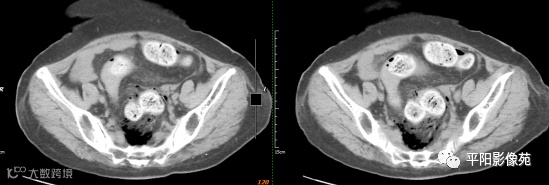

影像表现:乙状结肠前方可见不规则条状软组织密度影,边界不清,内见点状高密度;乙状结肠周围及骶前可见多发气体密度影。

影像表现:主要特点是腹腔内游离气体,可见肠壁增厚,边缘模糊,周围脂肪间隙模糊不清,并见不规则片状低密度,有粪石漏出时可见结节状高密度。